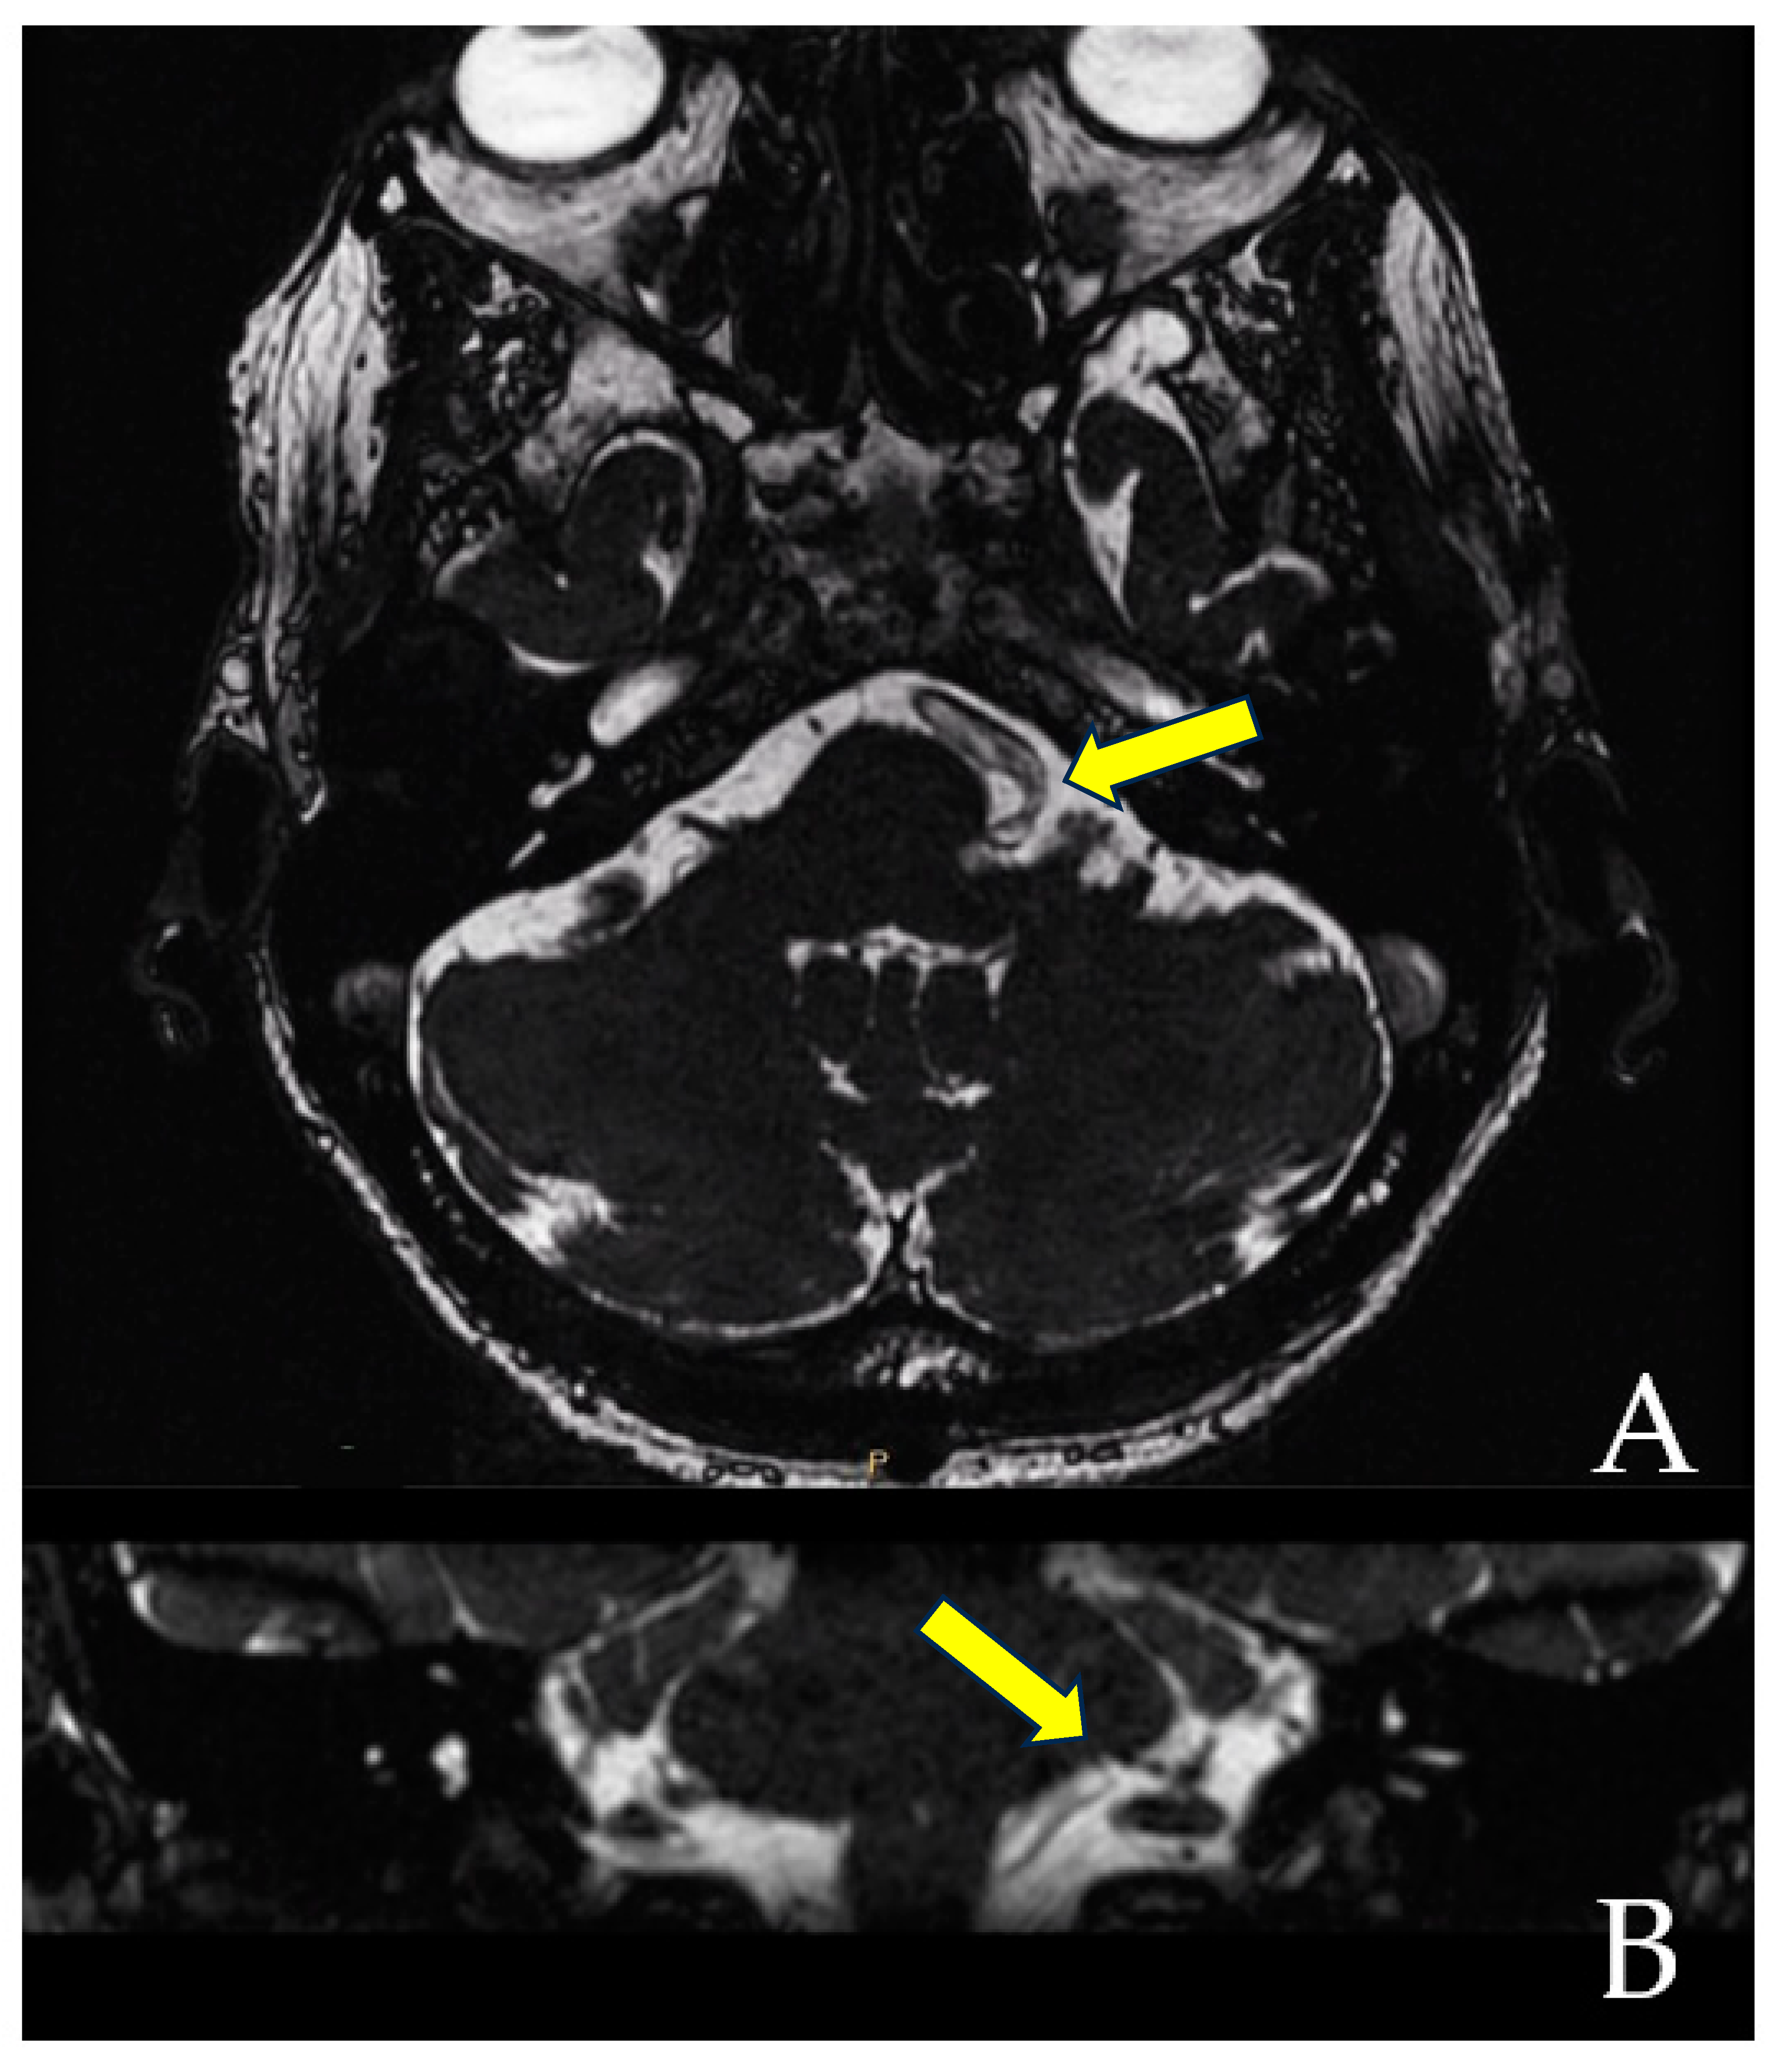

When the trajectory of the vessel is evaluated in the coronal view, it may be possible to visualize the vessel forming a loop superior and medial (towards the exit of the facial nerve) (Figure 1). When the MRI is visualized in the axial view, at the highest level of the loop in the coronal section, the proximity of the vascular structures to the pons may be seen in the axial view as if the artery was located inside of the brainstem, surrounded by the pons parenchyma (Figure 2).

The axial view gives the false impression that the artery is located inside the pons (A). However, the coronal view clearly demonstrates that the vessel does not enter the brainstem (B). The yellow arrows point to the local of the NVC.